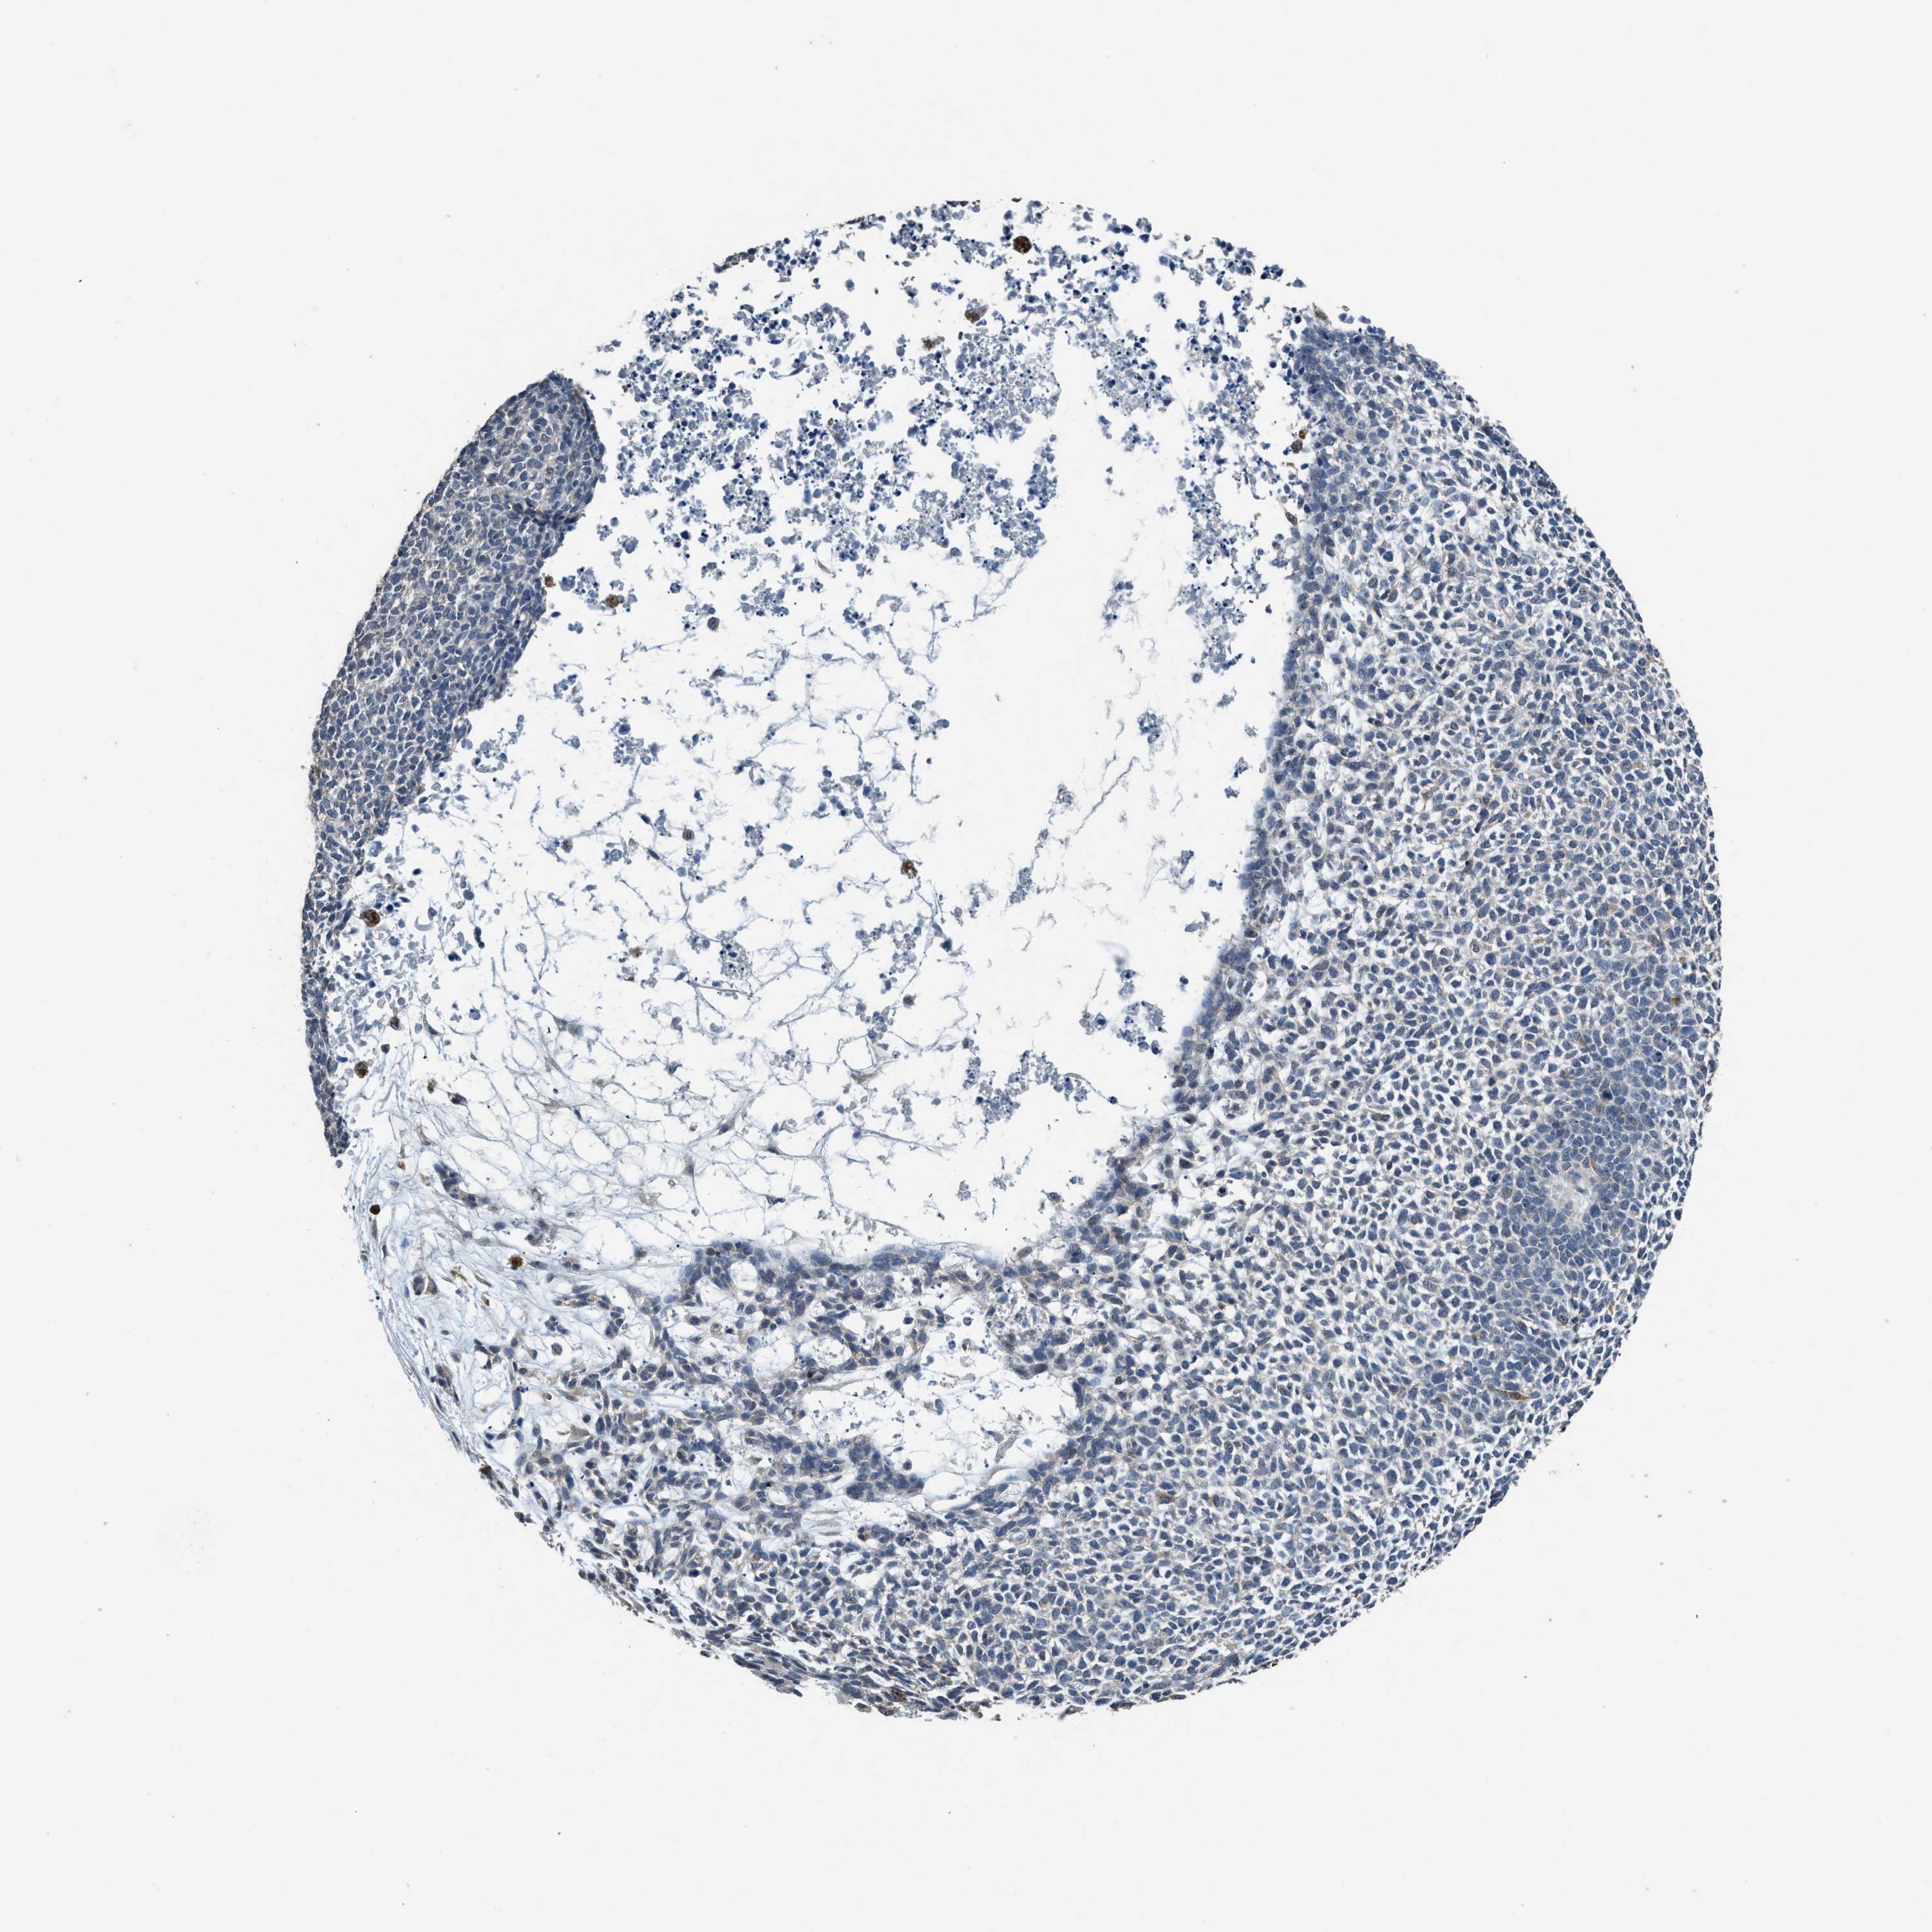

CANCER SKIN CANCER Show tissue menu

Basal cell and squamous cell cancer

SKIN CANCER - Protein expressioni

A mouse-over function shows sample information and annotation data. Click on an image to view it in a full screen mode. Samples can be filtered based on level of antibody staining by selecting one or several of the following categories: high, medium, low and not detected. The assay and annotation is described here.

Each image is clickable and will lead to virtual microscopy that enables deeper exploration of all samples and also displays staining intensity scores, fraction scores and subcellular localization as well as patient and tissue information for each sample.

Antibody HPA040066

Basal cell carcinoma